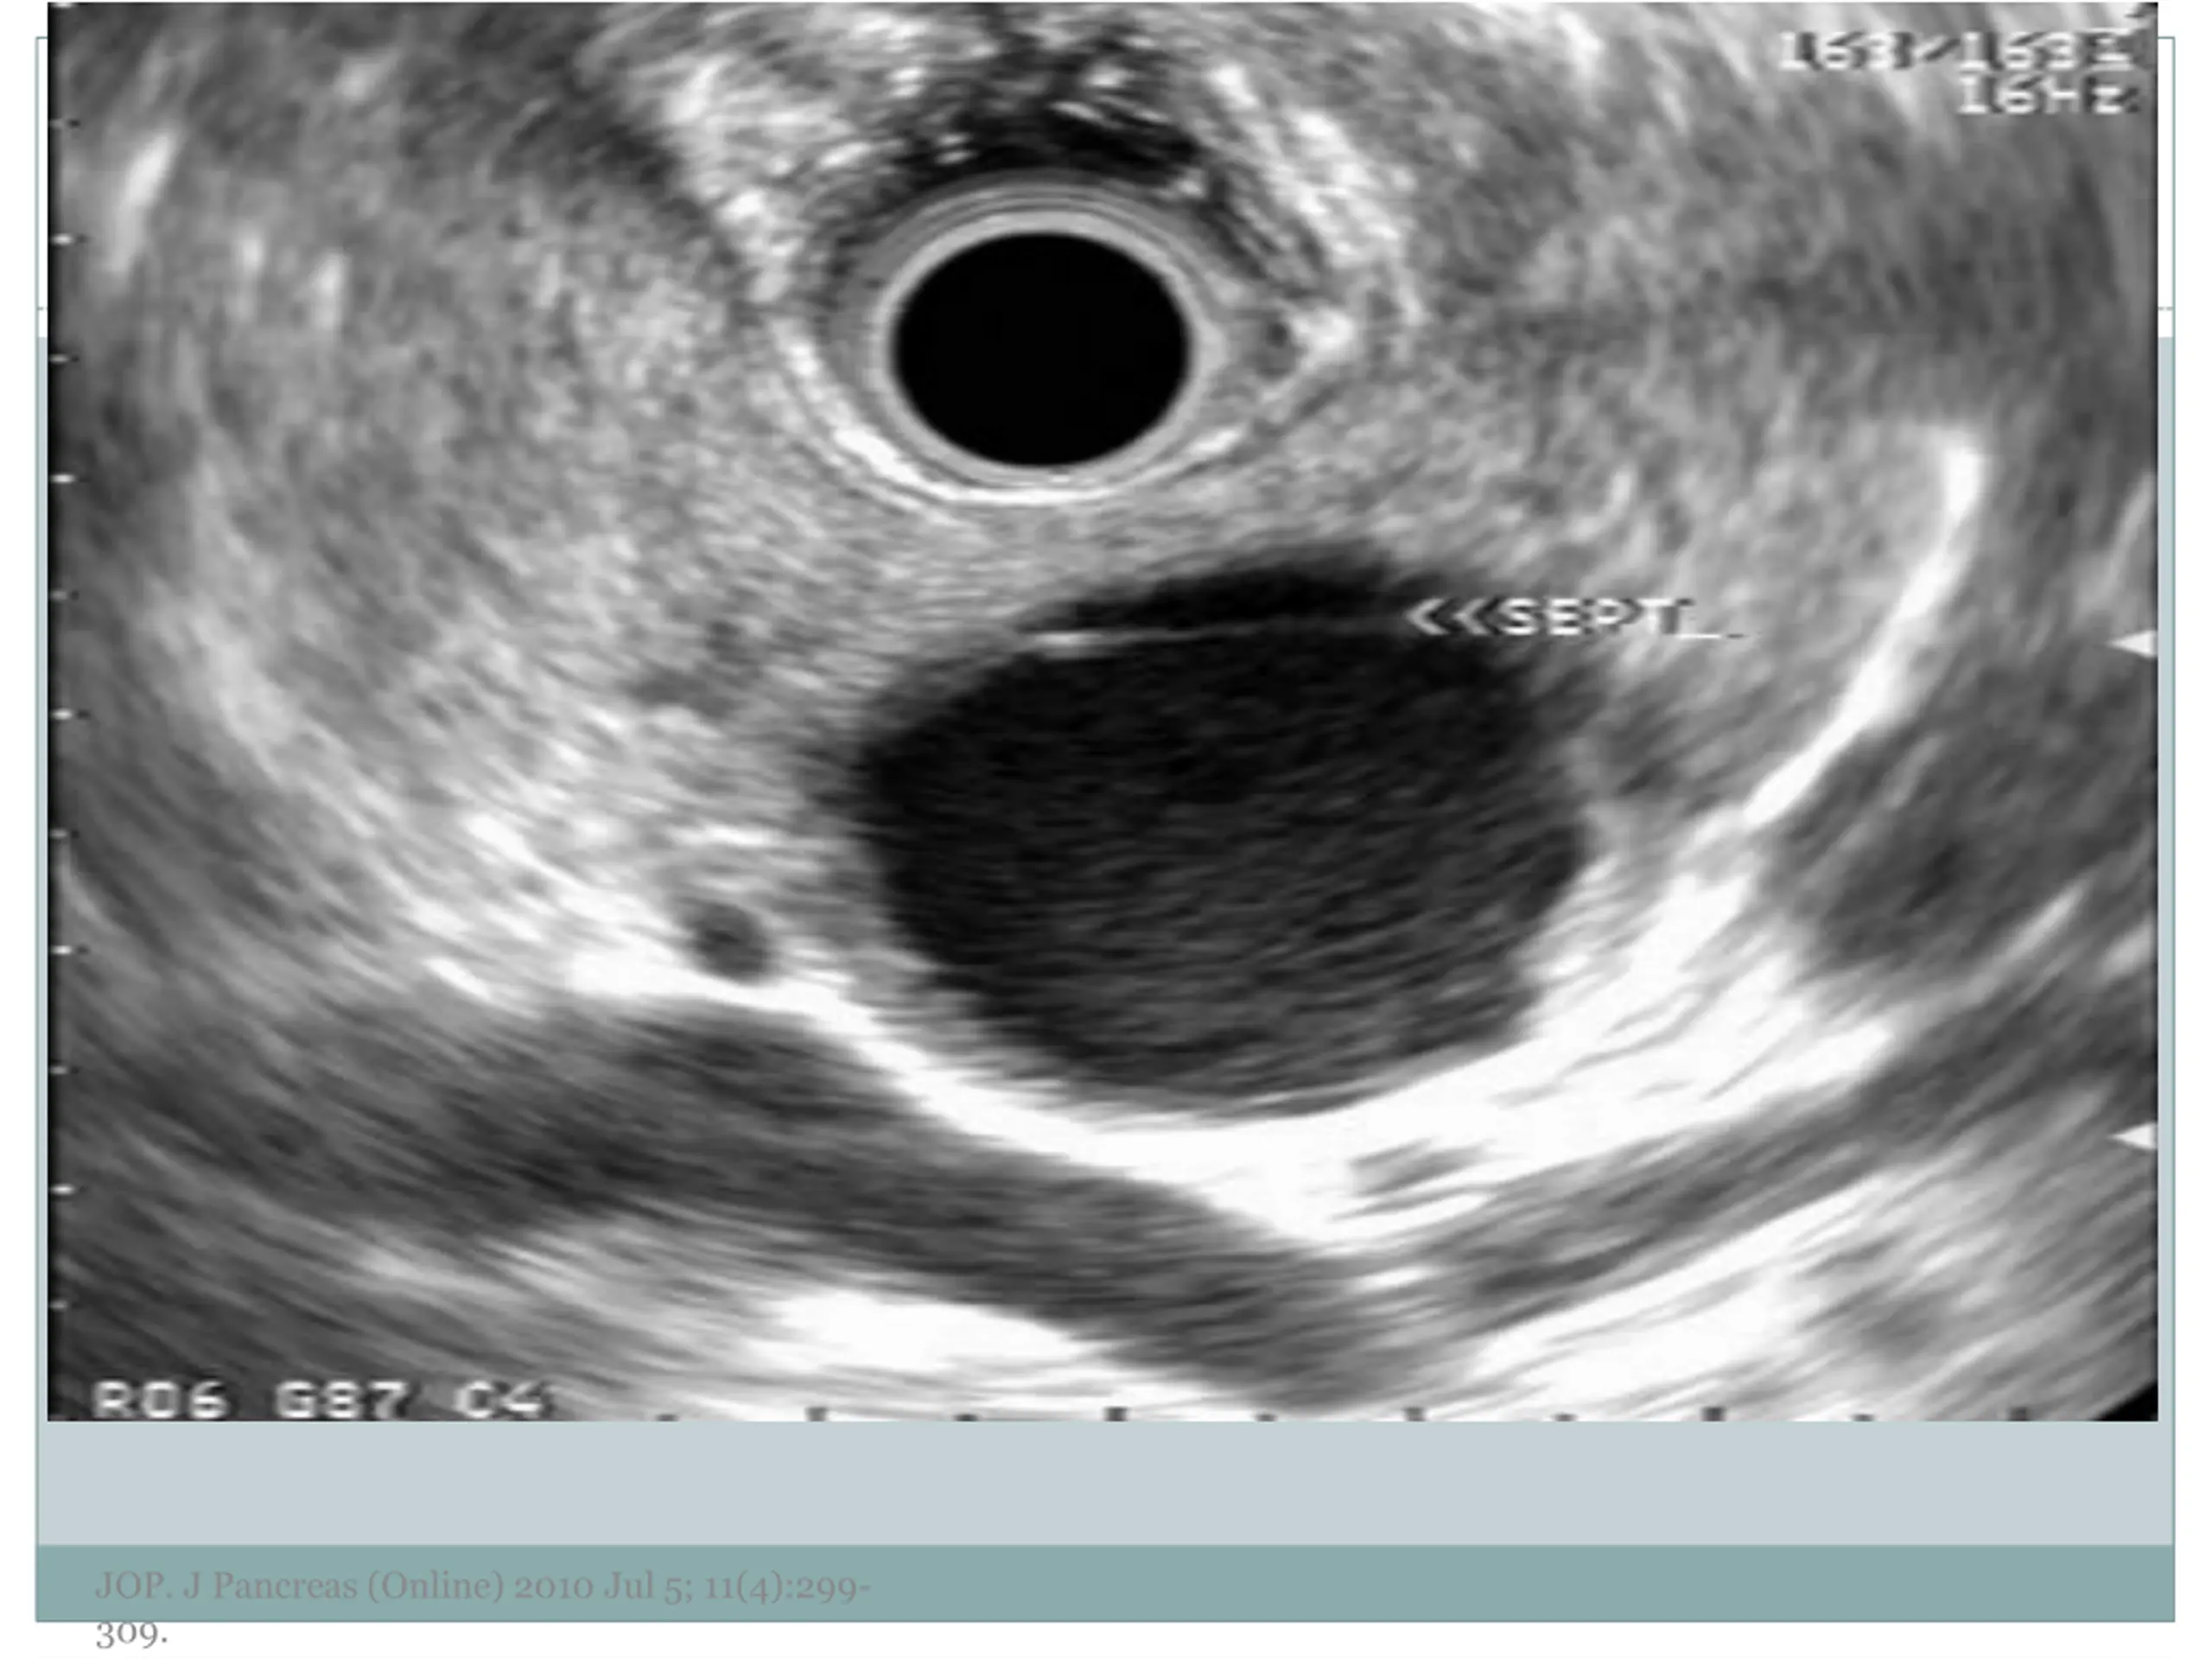

7. EUS Morphology Cyst wall Thick vs. thin Solid component Associated with malignancy Septations Micro vs. macrocystic Ductal abnormalities Main duct vs. side duct Number of cyst Lymphadenopathy EUS morphology can correctly differentiate mucinous from non-mucinous cystic lesions approximately 50% of the time JOP. J Pancreas (Online) 2010 Jul 5; 11(4):299- 309.

12. JOP. J Pancreas (Online) 2010 Jul 5; 11(4):299- 309.

13. JOP. J Pancreas (Online) 2010 Jul 5; 11(4):299- 309.